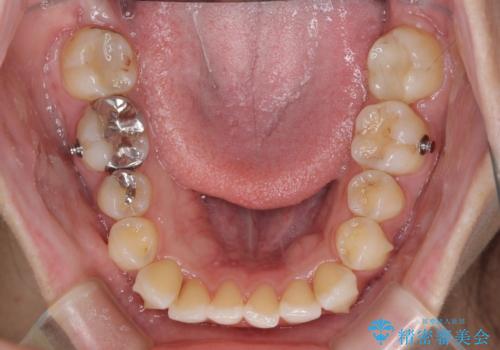

- 前歯のデコボコを気にして来院された患者様です。

主に下顎歯列全体の後方移動とIPR(歯と歯の間を削る)によってデコボコが解消するように設計し、インビザラインにより治療を行うこととしました。

舌突出癖がある方ですと、叢生が解消すると同時に前方に拡大されてしまいますが、ゴムかけをしっかりと行ってくださったこともあり、スッキリとした仕上がりとなりました。